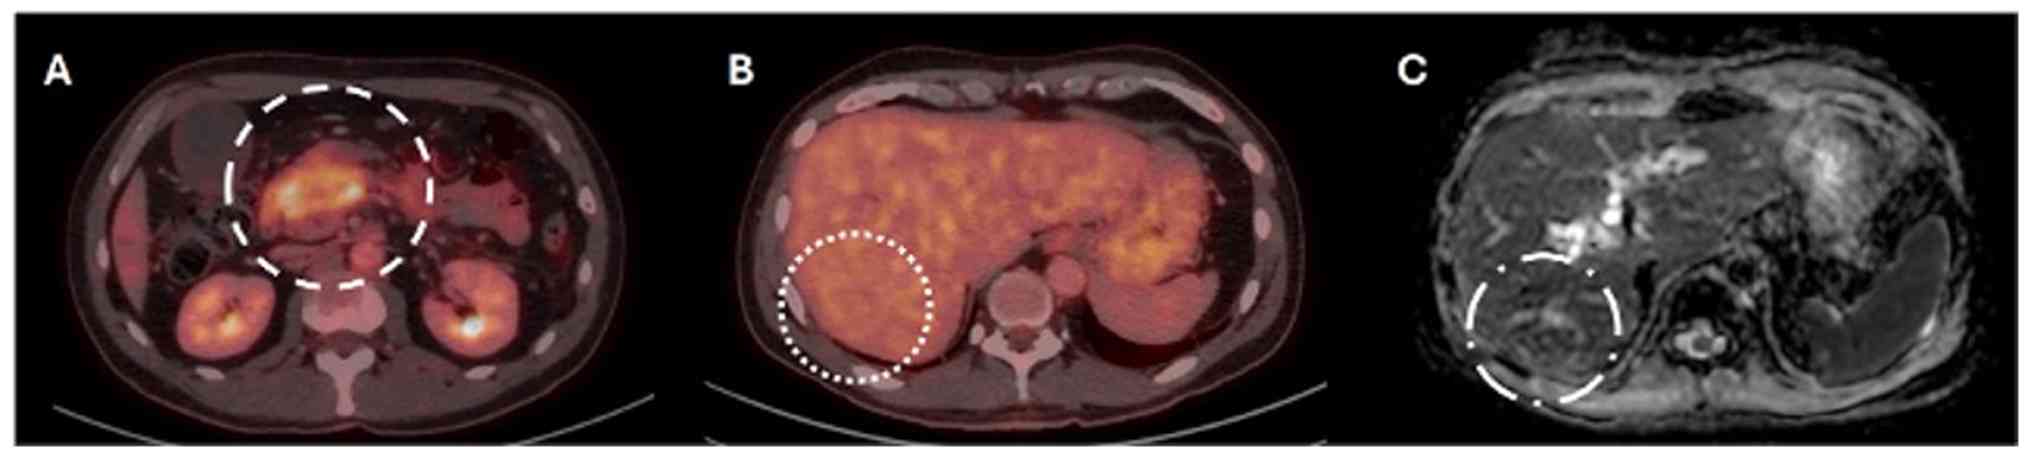

Radiological assessments indicated that the lesion in the initial portion of the duodenum lacked a discernible division plane, resulting in dilation of the central pancreatic duct and mild tail atrophy. Vascular structures, including the celiac trunk and superior mesenteric artery, appeared to maintain a division plane with the neoplasm (Fig. 2A). PET-CT revealed three focal hypodense liver lesions in segments VI, IVa, and II, all without metabolic activity (Fig. 2A). One lesion was suspicious for metastasis on PET-CT (Fig. 2B, dotted circle) and was subsequently confirmed on MRI, which demonstrated ring-like enhancement following gadolinium administration on ADC-weighted imaging (Fig. 2C, dotted circle). Several focal hepatic lesions with a non-suspicious appearance, such as hemangiomas, were also noted (Fig. 3). A mass was identified in the head of the pancreas (Fig. 3A, dashed circles), exhibiting perivascular invasion that compromised the superior mesenteric artery, inferior vena cava and abdominal aorta (Fig. 3C, dotted circle). The lesion appeared hyperintense on T2-weighted images (Fig. 3A-C, circles). Dixon-weighted sequence post-gadolinium administration demonstrated heterogeneous enhancement, which was highly suggestive of an aggressive neoplastic process (Fig. 3D, dashed circle). The out-of-phase image from the dual fast-field echo sequence displayed a heterogeneous signal intensity, indicating a hemorrhagic component and/or associated vascular changes (Fig. 3E, dashed circle). Furthermore, restricted diffusion of water molecules was observed on high-value diffusion-weighted imaging, supporting this diagnosis (Fig. 3F, dashed circle). Collectively, these imaging findings confirmed the diagnosis of an unresectable PDAC (T4N0M1; Grade IV).

FDG PET-CT in early-onset of

pancreatic ductal adenocarcinoma. (A) Imaging reveals increased FDG

uptake in the pancreatic head region (dashed circle). (B) A

suspected metastatic lesion in the liver was identified (dotted

circle). (C) The lesion was confirmed on MRI as a ring-like

enhancement after gadolinium administration on apparent diffusion

coefficient-weighted imaging (dot-dashed circle). FDG,

fluorodeoxyglucose, PET, positron emission tomography, CT, computed

tomography.

Figure 2

FDG PET-CT in early-onset of pancreatic ductal adenocarcinoma. (A) Imaging reveals increased FDG uptake in the pancreatic head region (dashed circle). (B) A suspected metastatic lesion in the liver was identified (dotted circle). (C) The lesion was confirmed on MRI as a ring-like enhancement after gadolinium administration on apparent diffusion coefficient-weighted imaging (dot-dashed circle). FDG, fluorodeoxyglucose, PET, positron emission tomography, CT, computed tomography.